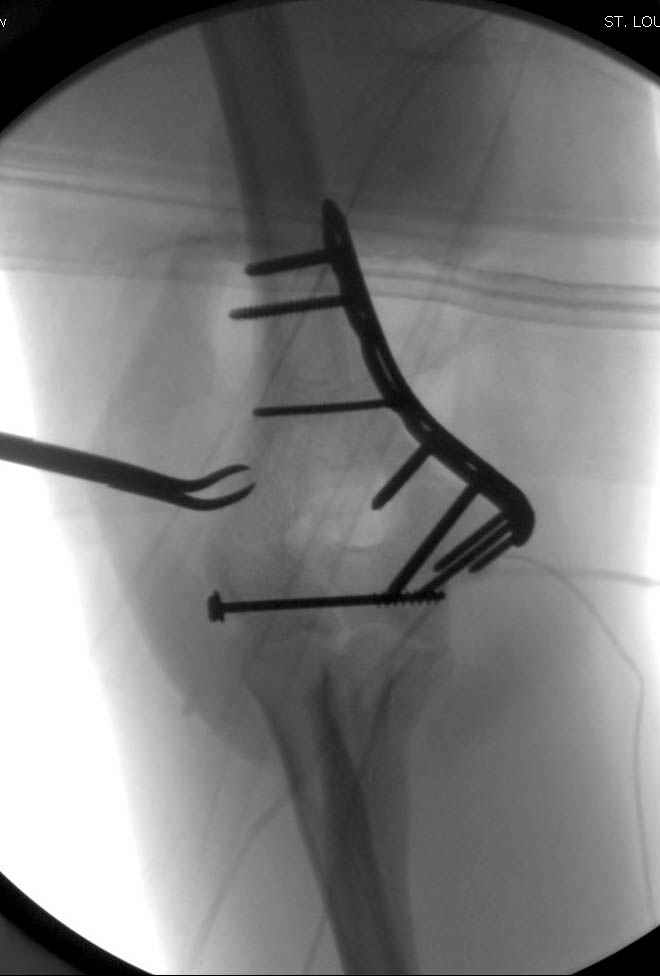

Примерный случай, только перелом был открытый, в задне-медиальной стороне рана около 2 см по характеру "изнутри кнаружи", неврологический статус со слабостью сгибания мизинца, также слабая абдукция и аддукция указательного пальца и сгибания в кисти.

Больному сделали обработку и наложили временный аппарат внешной фиксации плечо-предплечье.

На шестой день сделали открытую репозицию чрезлоктевым доступом двумя locking plate, локтевой нерв был ушибленным, после операции положительная динамика в Flexor Carpi Ulnaris. Фиксацию локтевого отростка произвели tension band technique с дополнительным шурупом.

Этапы операции на снимках....